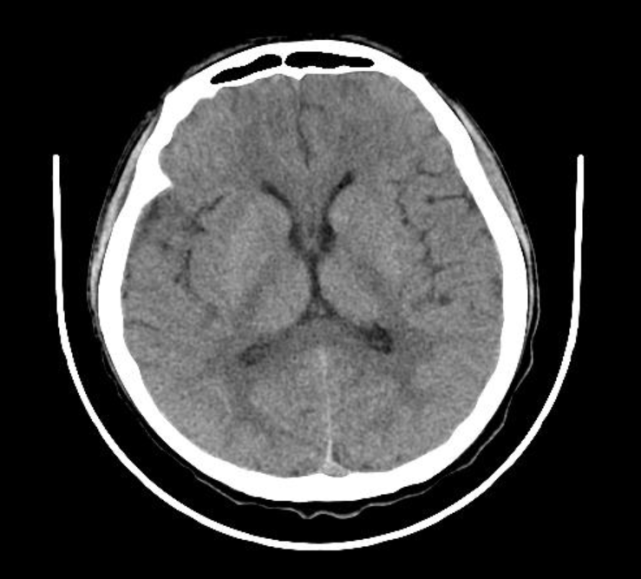

脑膜炎ct

ct内还没有病灶,考虑应该不是脑部肿瘤,大概率是感染引发的严重脑膜炎